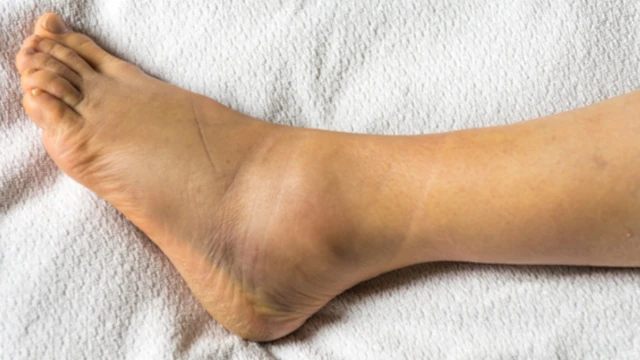

:format(webp)/ran_xuong_mat_ca_chan_bao_lau_thi_khoi_nguyen_nhan_va_dieu_tri_00_c793d84e0b.jpg)

Rạn xương mắt cá chân bao lâu thì khỏi? Rạn xương mắt cá chân là một chấn thương phổ biến, thường gặp ở những người chơi thể thao, vận động viên hoặc người gặp tai nạn. Tình trạng này gây ra nhiều đau đớn, ảnh hưởng đến khả năng vận động và sinh hoạt của người bệnh.

:format(webp)/ran_xuong_mat_ca_chan_0_fa7088314a.jpg)

Rạn xương mắt cá chân là một vấn đề y tế thường gặp khi xảy ra các tai nạn, bao gồm cả tai nạn giao thông và các tai nạn khác trong sinh hoạt hàng ngày. Xương cổ chân chịu áp lực lớn từ trọng lượng cơ thể và các hoạt động vận động, vì vậy khi bị tổn thương, nó có thể gây ra đau đớn, khó khăn trong việc di chuyển và ảnh hưởng đến chất lượng cuộc sống của người bệnh.